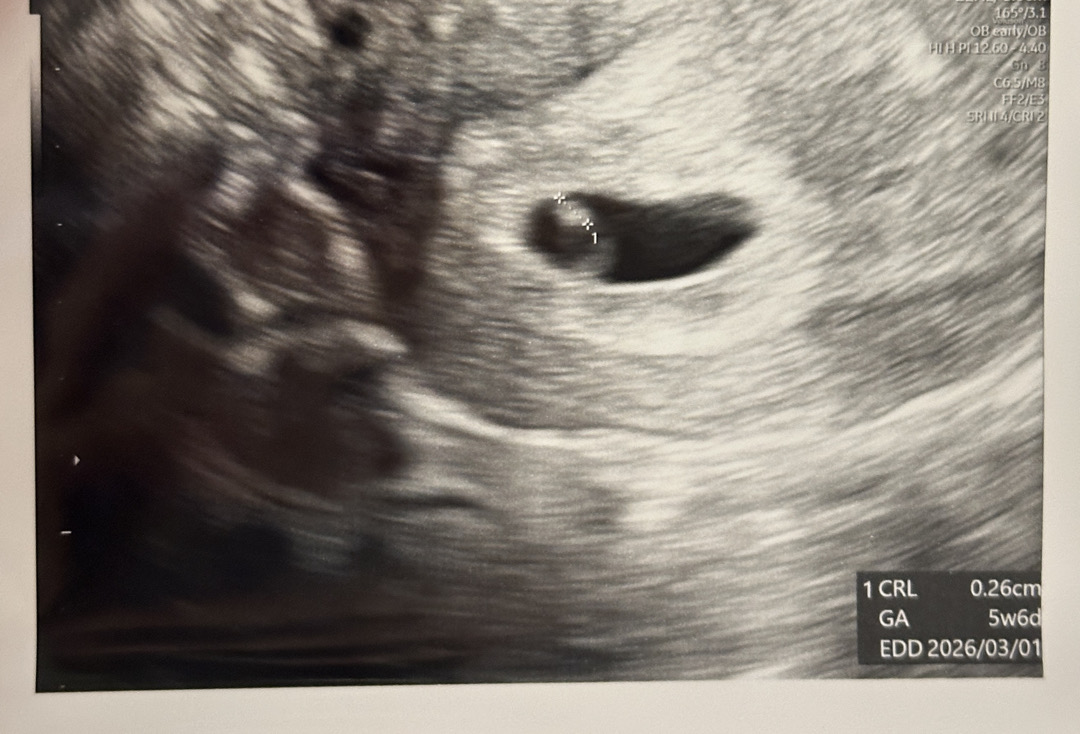

5주4일차에 아기집 보고왔어요

막생 5/27 어제 병원가서 아기집 봤어요 난황이랑 애기도 보이고 애기 심장 뛰는것도 보이더라고요! 신기ㅠㅠ 심장 초음파 듣기에는 아직 작아서 다음주에 한번 더 가요! 0.26cm가 심장도 뛰고 대견...

소리는 못듣고 뛰는거 보기만 했어요! 콩닥콩닥 하더라고요ㅎㅎ